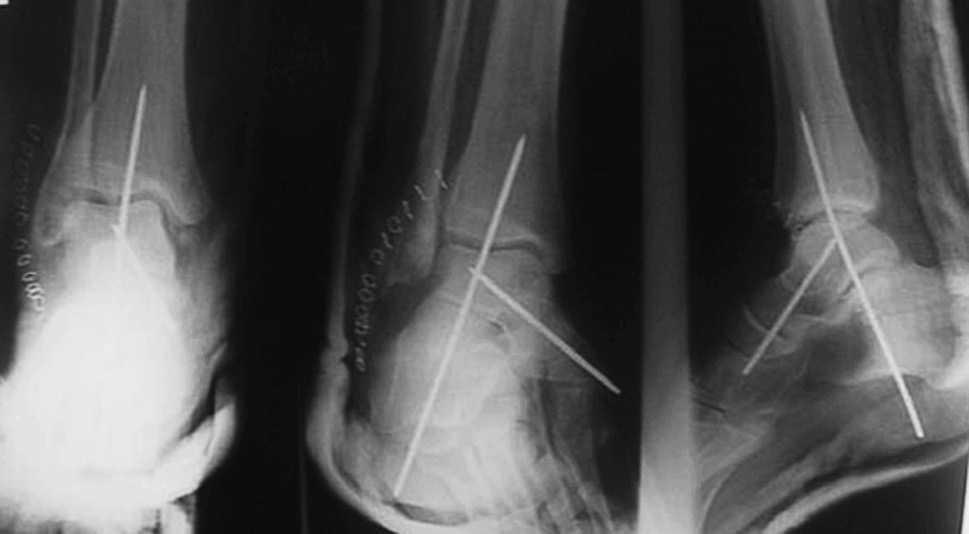

En las fracturas del cuerpo del astrágalo (7 casos) se realizó reducción abierta mediante un abordaje medial con osteotomía del maléolo tibial para visualizar todos los planos de la fractura y fijación interna (RAFI) con tornillos o agujas de Kirschner, o ambos. En 2 casos se realizó un abordaje bilateral debido a la complejidad de la fractura (fig. 6).

Fig. 6. --Fractura abierta de cuello de astrágalo (tipo III de Hawkins) y tratamiento realizado. Radiografías a los 16 meses.

Fig. 6. --Open fracture of the astragalus neck (Hawkins type III) and treatment carried out. Radiographies at 16 months.